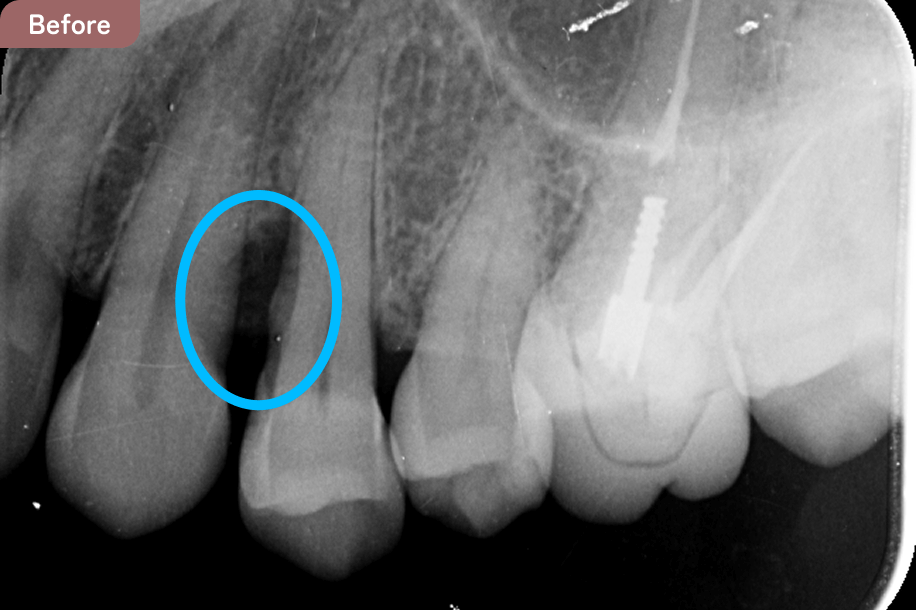

青丸の部分に再生療法を行った結果、骨の再生が認められる。